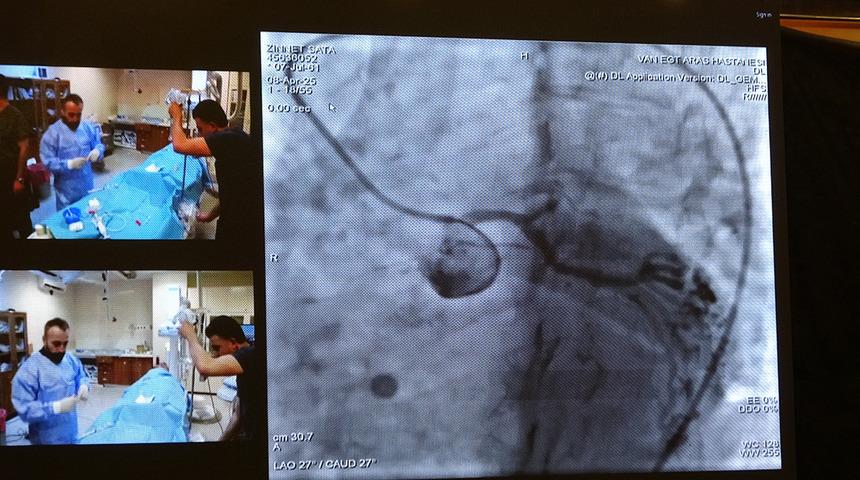

Van Eğitim ve Araştırma Hastanesi’nin kateter laboratuvarlarında gerçekleştirilen 12 canlı vaka oturumunda; sol ana koroner müdahaleleri, bifurkasyon ve kompleks PFO/ASD vakaları, tam tıkalı damar (CTO) işlemleri, karotis, EVAR, TAVI, apendiks kapama, septal ablasyon ve mitral balon valvüloplasti gibi işlemler başarıyla uygulandı.

Hastanede gerçekleştirilen canlı vaka işlemlerinin Türkiye’deki tüm kardiyologlar tarafından izlenebildiğini belirten Van Eğitim ve Araştırma Hastanesi Başhekimi Doç. Dr. Remzi Sarıkaya ise "Bu bizim için son derece önemli bir adım. Gerçekleştirilen vakaların tamamı oldukça zorlu vakalar olup, geçmişte bu tür işlemler bu bölgede yapılmazken, son dönemde hem ilimizde ciddi bir şekilde yapılmaya başlanmış hem de tecrübe aktarımı noktasında önemli bir aşama kaydedilmiştir. Tüm ekip arkadaşlarımı bu başarılarından dolayı kutluyorum. Peki, bu canlı vakalar nelerdir? Ameliyatsız aort kapak değişimi, kalp deliklerinin kapatılması, daha önce tek seçenek olarak ameliyatla tedavi edilen ciddi ana koroner lezyonları ve çatallanma olarak adlandırılan bifurkasyon stentlemeler, sol atriyal apendiks kapama dediğimiz pıhtı atan deliklerin kapatılması, aort damarda var olan anevrizmaların kapatılması gibi son derece zor ve karmaşık vakalar burada canlı yayında gerçekleştirilerek tecrübe aktarımına imkan sağlamaktadır. Bu tür bir toplantının ilimizde yapılması ve bu tecrübe aktarımının gerçekleştirilmesi bizim için büyük bir gurur kaynağıdır" dedi.